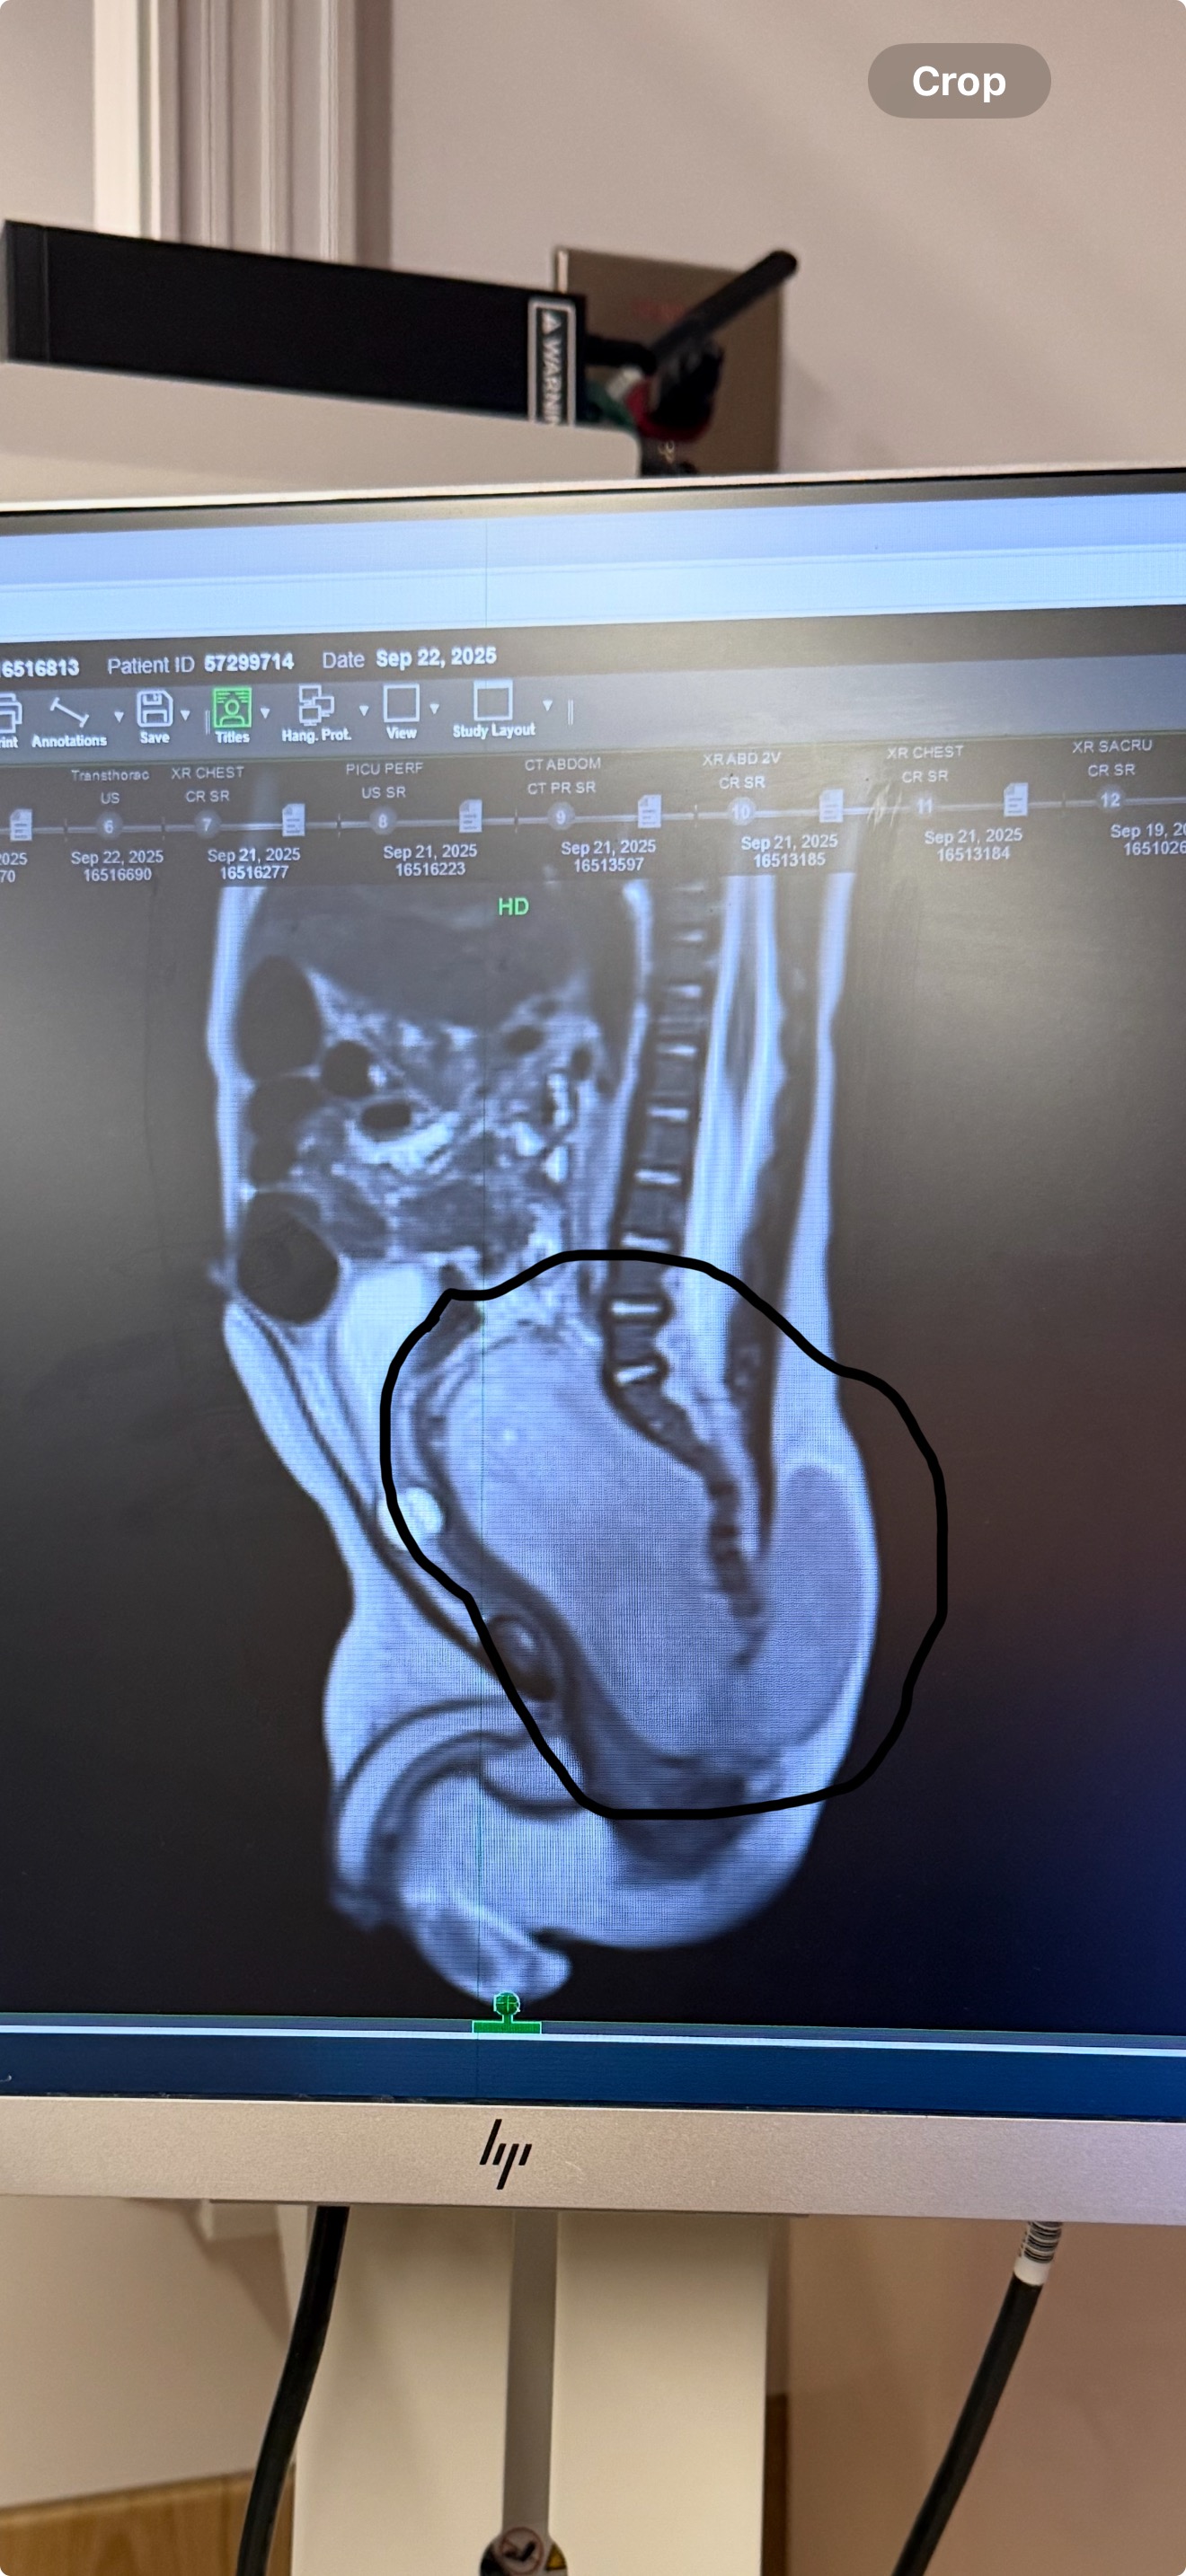

My name is Lakeisha, and I’m reaching out with a heavy heart. My sweet baby boy, Loyal, is only five months old and has already been through more than most of us could imagine. Recently, he was diagnosed with Neuroblastoma, a rare and aggressive form of childhood cancer.

What started as a few concerning symptoms quickly turned into a nightmare. We spent a full month in the hospital as doctors ran tests, performed two surgery procedures, and still working on the right treatment to help our little fighter. Watching my tiny baby hooked up to tubes and monitors has been the hardest thing I’ve ever experienced.